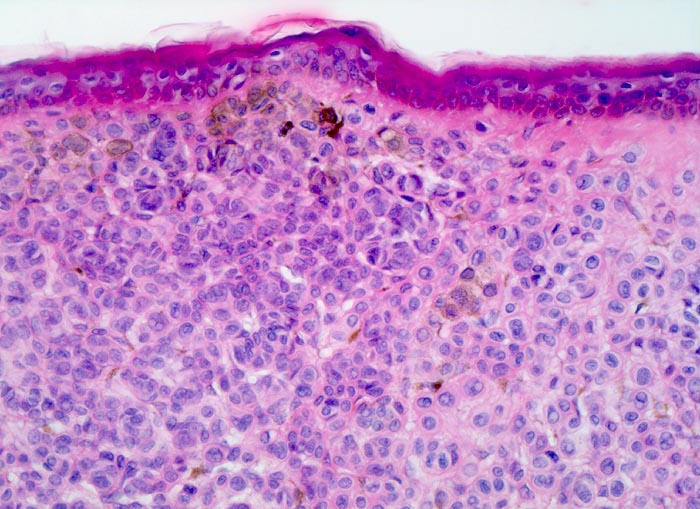

dermaler Naevuszellnaevus

benigner Tumor

Haut, Rumpf

Haut

Dünne Epidermis ohne Infiltrate von Naevuszellen. Die Naevuszellen im Corium bilden dichtliegende Zellballen. Vor allem in den oberflächlichen Naevuszellen lässt sich braunes Melaninpigment nachweisen.

Graubraune, leicht erhabene, scharf begrenzte Hautveränderung über dem Schulterblatt.

Histologie

200